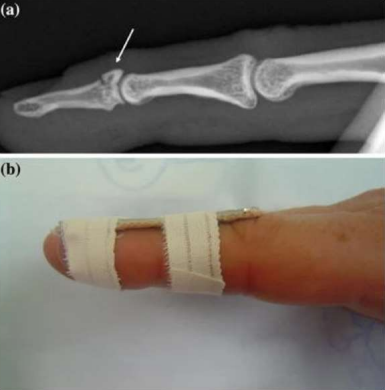

Figure 03 (a) Lateral radiograph of a mallet fracture (b) Dorsal splint used for mallet finger (soft tissue or bony mallet). Notice slight extension pre-bent into splint to assist in reduction of the avulsed fracture fragment seen in Fig. 3a. Patients treated with dorsal splints should be examined frequently for dorsal skin breakdown under the splint